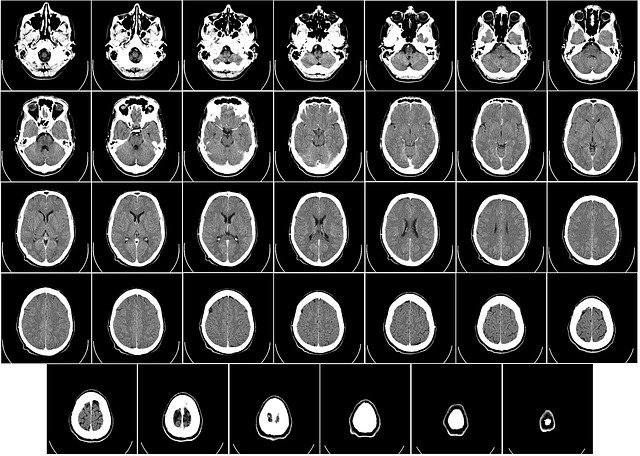

조영제는 방사선검사에서 조직에 투여하여 인위적으로 흡수차이를 일으켜서 색상의 대조도를 높이는 악품입니다. CT조영제는 CT촬영하기전 촬영사진의 선명도를 위해 주입하는 약품이라고 보시면 됩니다.

조영제를 투여하게 되면 병변의 윤곽형태를 보다 선명하게 관찰할 수 있어, 촬영으로 인한 진단을 보다 정확하게 할 수 있는 장점이 있는데요. 사용부위로는 뇌, 폐, 위, 간 등... 거의 모든 내장기관의 질환과 손상을 파악하는데 이용됩니다.